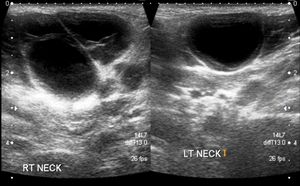

On palpation, the swelling was non-tender, soft, and mobile but did not feel fluid-filled. Here, view ultrasound findings and propose your diagnosis.